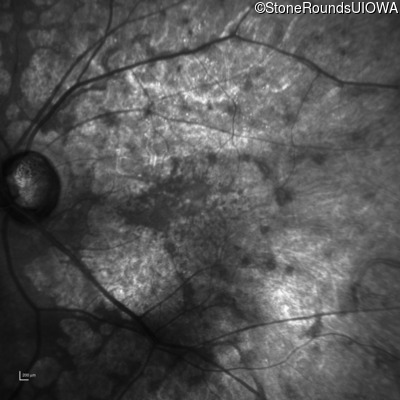

This 81 year old man began using a flashlight to read menus in his 40's. At age 75 his ophthalmologist noticed abnormal fundus findings and referred him to a retina specialist.

Diagnosis & molecular findings

| Late Onset Retinal Dystrophy | C1QTNF5 | Ser163Arg AGC>AGA | AD |